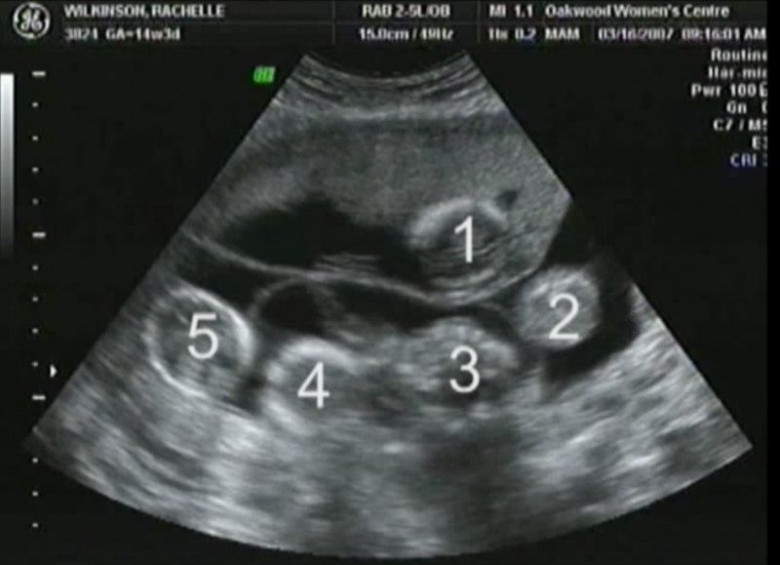

Այս հղի կինը եկել էր հետազոտման, սակայն բժիշկը կորցրեց խոսելու ունակությունը, երբ նայեց ՈՒՁՀ սարքի էկրանին

Նման օրինակ է Տեխասի բնակիչներ Ռեյչլւ ու Ջեյսոնի պատմությունը։ Ինչքան էլ զարմանալի լինի այս պատմությունը, հավատացեք՝ այս ամուսնինների զարմանքն էլ ավելի մեծ էր։ Նրանք արդեն մի քանի տարվա ամուսիններ էին ու արդեն 2 երեխա ունեին, սակայն ուզում էին 3-րդն էլ ունենային։ Ցավոք, նրանց մոտ չէր ստացվում։

Բայց ամուսինները չէին հանձնվում ու սկսեին բուժում անպտղության դեմ։ Ռեյչլին հորմոններ նշանակեցին ու շուտով հույսի հայտնվեց. կինը նորից հղի էր։ Երբ Ռեյչլը գնաց առաջին ՈՒՁՀ-ին, բժիշկը 2 սրտի բաբախում նկատեց. նրանք երկվորյակներ էին ունենալու։ Ընտանիքը երջանկության մեջ էր։

Բայց այսքանով պատմությունը չի վերջանում։ Երբ հաջորդ անգամ բժիշկը ՈՒՁՀ էր անցկացնում, Ռեյչլը չէր կարողանում հավատալ իր աչքերին. սրտի բաբախյունները երկուսը չէին ու նույնիսկ երեքն էլ չէին։ Բժիշկը հաշվեց 5 երեխա։

Ամուսինները պարզապես շշմած էին։ Բազմապտուղ հղիությունը հազվադեպ է պատահում, բայց երբեմն լինում է այդպես անպտղության դեմ բուժման արդյունքում։ Նրանք դժվար ընտրության առաջ էին կանգնած։ Բժիշկների կանխատեսումները լավատեսական չէին. հղիությունը բարդ էր լինելու, ու պարզ չէր, կապրեն արդյո՞ք բոլոր 5 երեխաները։ Բայց նրանք որոշեցին պահել հինգին է։